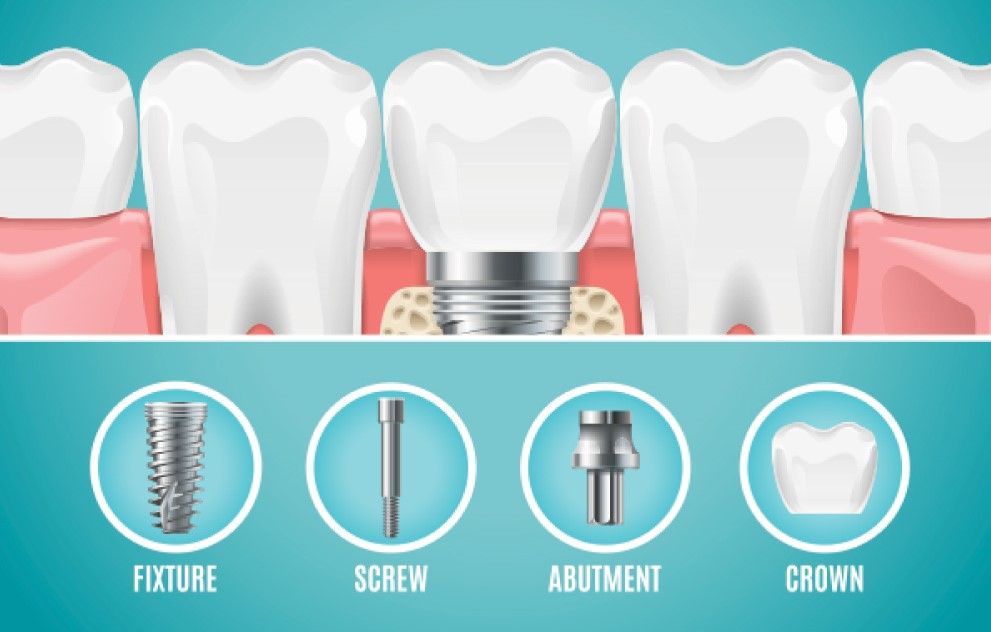

ایمپلنت نوعی روش کاشت دندان به صورت دائمی و ماندگار است که اگر شخص به توضیحات و توصیههای دندانپزشکی که کارهای ایمپلنت وی را انجام داده است توجه و عمل کند تا آخر عمر میتواند از مزایای آن بهره ببرد. در فرایند ایمپلنت کردن دندان، ایمپلنت در واقع نوعی پیچ فلزی است که درون استخوانهای فک جای میگیرد و سپس در قسمت بیرونی آن، رویهای به شکل دندان واقعی قرار میگیرد و ظاهری کاملاً طبیعی به دندان جدیدی که به صورت مصنوعی در دهان جای گرفته است خواهد بخشید. عبارت مصطلح در دندانپزشکی برای پیج، پایه و برای قسمت رویهی دندان تاج است و میبایست برای معرفی از نامهای تخصصی آن استفاده نمود. قسمت پایه ایمپلنت معمولاً از جنس تیتانیوم ساخته میشود، چرا که سازگاری بالای تیتانیوم با بدن و استخوانهای فک انسان از بروز هرگونه آسیب استخوانی، لغزش، سر و صدا و …. جلوگیری میکند.

مراحل انجام ایمپلنت دندان

- مراجعه به کلینیک دندانپزشکی معتبر

- معاینه توسط دندانپزشک

- انجام آزمایشات و عکسبرداریهای لازم

- کشیدن دندانهای آسیب دیده

- آماده سازی فک بیمار

- کشت پیچ ایمپلنت در استخوان

- منتظر ماندن برای شکل گیری استخوان فک به خوبی

- ساخت پروتز قسمت رویه

- کشت تاج برروی لثهی بیمار